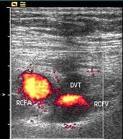

If a blood clot develops inside a vein, however, it can block the normal flow of blood and cause temporary and long-term problems. This can result in pain, tenderness and swelling of the leg. When a blood clot occurs in one of the main veins of the body (usually a leg or pelvic vein after hip surgery) it is called a deep vein thrombosis or DVT. These clots become life threatening if they move to the heart, lungs or brain. If a clot breaks loose from a vein, it may travel through the heart and can block lung arteries. This is called a pulmonary embolism or PE. A PE can cause sharp chest pain, shortness of breath, coughing up blood or passing out. If the clot is severe enough, it can be life threatening or fatal.

The medical term for a blood clot in the blood vessel is a thrombus. Deep vein thrombosis (DVT) is a formation of a blood clot in one of the deep veins of the body, particularly in the leg or pelvis. It is a problem that can be asymptomatic (silent), or in the worse case scenario, fatal. Death can occur if a blood clot which forms in the deep veins of the body breaks off and travels to the lungs, heart or brain and causes severe overload of the capacity to breath or pump blood. Some doctors think that even a silent blood clot can cause chronic swelling or skin ulcerations, a difficulty called post-phlebitic syndrome.